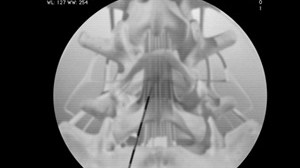

• Lumbar Epidural Steroid Injection

This injection procedure is performed to relieve low back and radiating leg pain. Steroid medication can reduce the swelling and inflammation caused by spinal conditions.